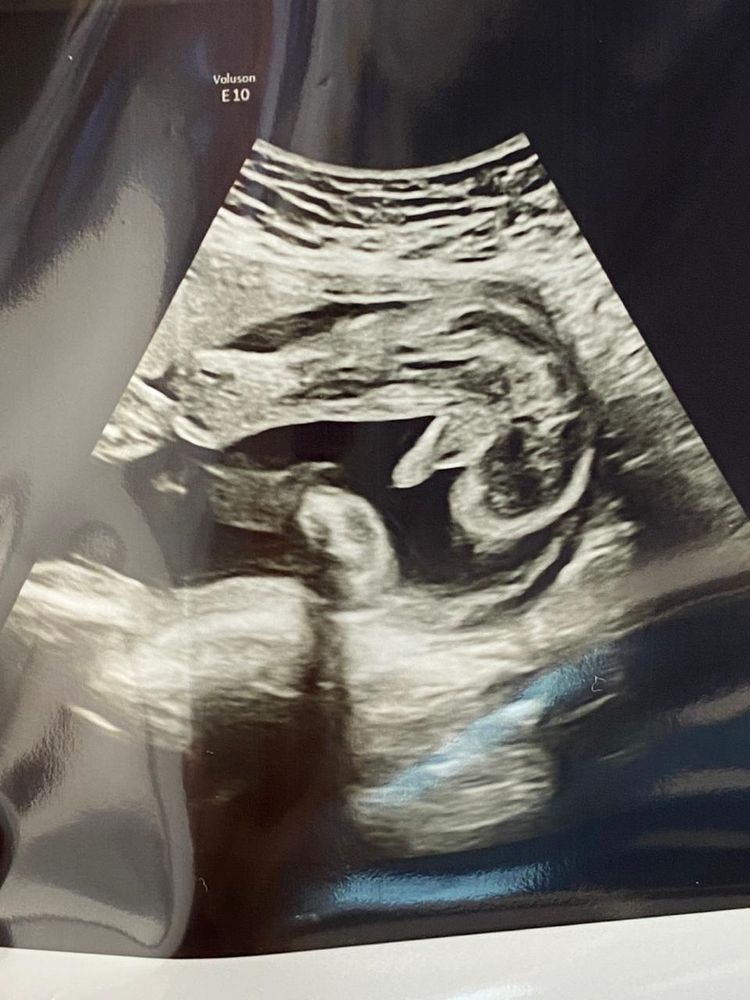

Екатерина, малышок у вас видимо крутится вертится, не хочет маме показывать кто он))) у меня ноги раздвинул так, что там с первой секунды все понятно было😂🤭 Изображение

30.09.2023

Жужа, тут даже я поняла, которая вообще ничего не понимает на снимках узи 😆😆😆